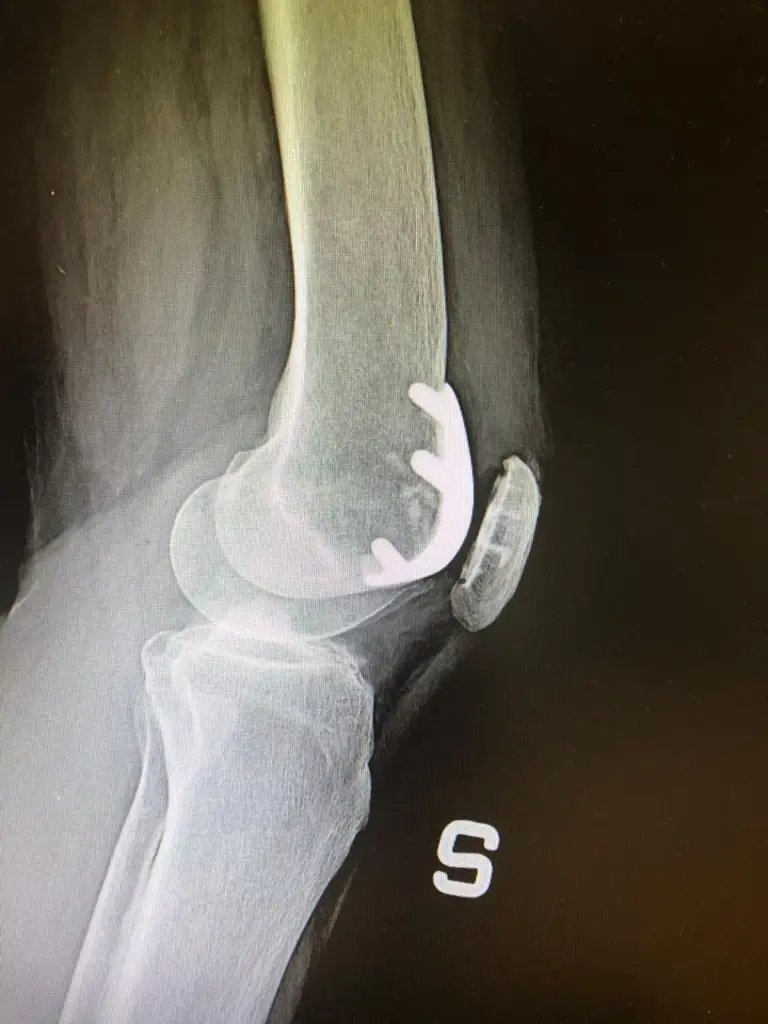

[vc_row rt_row_background_width=”fullwidth” rt_row_content_width=”default” rt_row_style=”default-style” rt_row_borders=”” rt_row_shadows=”” rt_row_paddings=”true” rt_bg_effect=”classic” rt_bg_image_repeat=”repeat” rt_bg_size=”cover” rt_bg_position=”right top” rt_bg_attachment=”scroll” rt_bg_video_format=”self-hosted”][vc_column rt_column_shadow=”” rt_bg_image_repeat=”repeat” rt_bg_size=”auto auto” rt_bg_attachment=”scroll”][vc_column_text]Patologia che riguarda un over 60 su 3, l’artrosi del ginocchio, conosciuta anche come gonartrosi, si contraddistingue per la degenerazione della cartilagine che riveste il femore e la tibia. In alcuni casi, può essere coinvolta anche quella della rotula.

Nei casi in cui l’artrosi al ginocchio è talmente avanzata da compromettere la qualità della vita del soggetto che ne soffre (i principali campanelli d’allarme in questo caso sono il dolore e la limitazione funzionale), la soluzione da adottare è il ricorso alla chirurgia protesica. Quest’ultima, per rispondere a un’esigenza sempre più forte soprattutto dal punto di vista numerico (negli ultimi decenni l’incidenza è aumentata notevolmente e il problema riguarda spesso anche persone di età inferiore ai 60 anni), è stata interessata da innovazioni rilevanti, come per esempio la realizzazione di impianti protesici customizzati. Nelle prossime righe, parlerò meglio del workflow che permette di crearli e soprattutto dei vantaggi che comporta il loro utilizzo.

Il processo di realizzazione delle protesi di ginocchio customizzate parte dall’esecuzione di una TAC, indagine che consente di avere a disposizione una ricostruzione tridimensionale del ginocchio del paziente.

I risultati della TAC vengono infatti sottoposti all’elaborazione da parte di un software, che restituisce dati utili innanzitutto alla creazione delle maschere PSI (Patient Specific Instrument), modelli che permettono di ottimizzare il posizionamento della componente protesica, che viene realizzata rispettando l’allineamento cinematico.[/vc_column_text][/vc_column][/vc_row][vc_row rt_row_background_width=”fullwidth” rt_row_content_width=”default” rt_row_style=”default-style” rt_row_borders=”” rt_row_shadows=”” rt_row_paddings=”true” rt_bg_effect=”classic” rt_bg_image_repeat=”repeat” rt_bg_size=”cover” rt_bg_position=”right top” rt_bg_attachment=”scroll” rt_bg_video_format=”self-hosted”][vc_column rt_column_shadow=”” rt_bg_image_repeat=”repeat” rt_bg_size=”auto auto” rt_bg_attachment=”scroll”][vc_column_text]